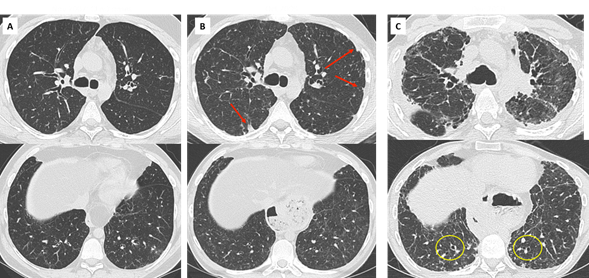

Figure 5. early detection and evolution of RAS in a 24 yo man, who underwent bilateral LT in 2007 for cystic fibrosis. Axial and coronal images of CT scans at optimal spirometry (A), 4 months before the diagnosis of CLAD (B), 8 (C) and 22 months (D) after the diagnosis of CLAD.

(A) May 2008: normal CT scan.

(B) August 2008: first visualization of subtle subpleural ground glass areas and consolidation (red arrows), considered nonspecific and treated with antibiotics. The diagnosis of CLAD was confirmed in December 2008 with a RAS profile.

(C) August 2009: rapid evolution towards destructive, upper predominant cystic lesions and interstitial fibrosis.

(D) October 2010: late RAS. CT changes suggestive of pleuroparenchymal fibroelastosis with dense subpleural fibrosis and pleural thickening, dramatic loss of volume of the upper lobes.